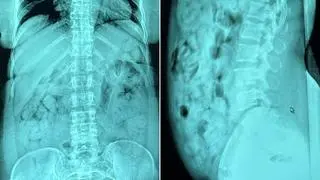

Funkcjonariusze przewieźli ją do szpitala w Bergamo, gdzie przeprowadzone badania radiologiczne potwierdziły, że 46-latka połknęła 120 kapsułek umieszczonych w sztywnych plastikowych pojemnikach owiniętych taśmą klejącą. Zawierały heroinę o łącznej masie 1393 gramów. Włoskie służby ujawniły zdjęcie przemycanych narkotyków.

Kobieta połknęła 120 kapsułek z heroiną